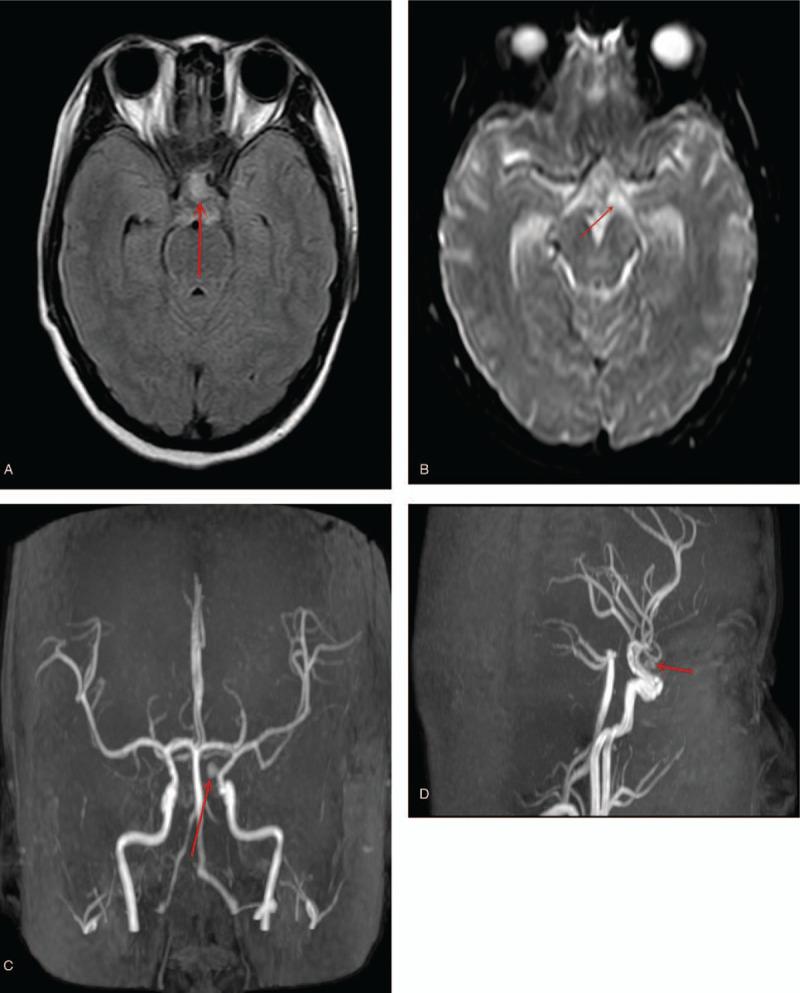

Emergency obstetric ultrasound scan done confirmed 32 weeks' twin gestation, whereas magnetic resonance imaging established hemorrhage in the suprasellar cistern and the subarachnoid space. Magnetic resonance angiography revealed a dissected aneurysm in the ophthalmic segment of the left internal carotid artery.

急诊产科超声检查证实为 32 周的双胎妊娠,而磁共振成像显示鞍上池和蛛网膜下腔出血。磁共振血管造影显示左侧颈内动脉眼段夹层动脉瘤。